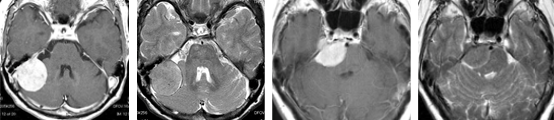

錐体斜台部髄膜腫

この部位は脳神経がすだれのように走行しており、腫瘍により脳幹・脳神経(外転神経・顔面神経・聴神経など)が圧迫されると物が2つに見えたり、耳が聞こえなくなったり、さらに腫瘍のサイズが大きくなると生命に危険な状態となります。

(術前MRI)

(術後MRI)

このように比較的大きい腫瘍が脳幹を圧迫している場合は、重篤な症状をきたし生命に危険が伴う可能性があるため、早急に手術が必要です。

一方、この腫瘍は小さいのですが、三叉神経の圧迫により耐えがたい顔面痛により発見された髄膜腫です。当初手術を躊躇し鎮痛剤を服用しながら経過観察しておりましたが、症状が改善されなかったため、手術を行いました。腫瘍は全摘され、術前に鎮痛剤で改善しなかった顔面痛は、術後には完全に消失しました。勿論、鎮痛剤を服用する必要も全くなくなりました。思い切って手術を決断してよかったと大変満足いただけました。 このように手術をしないと症状が改善されない髄膜腫もあります。